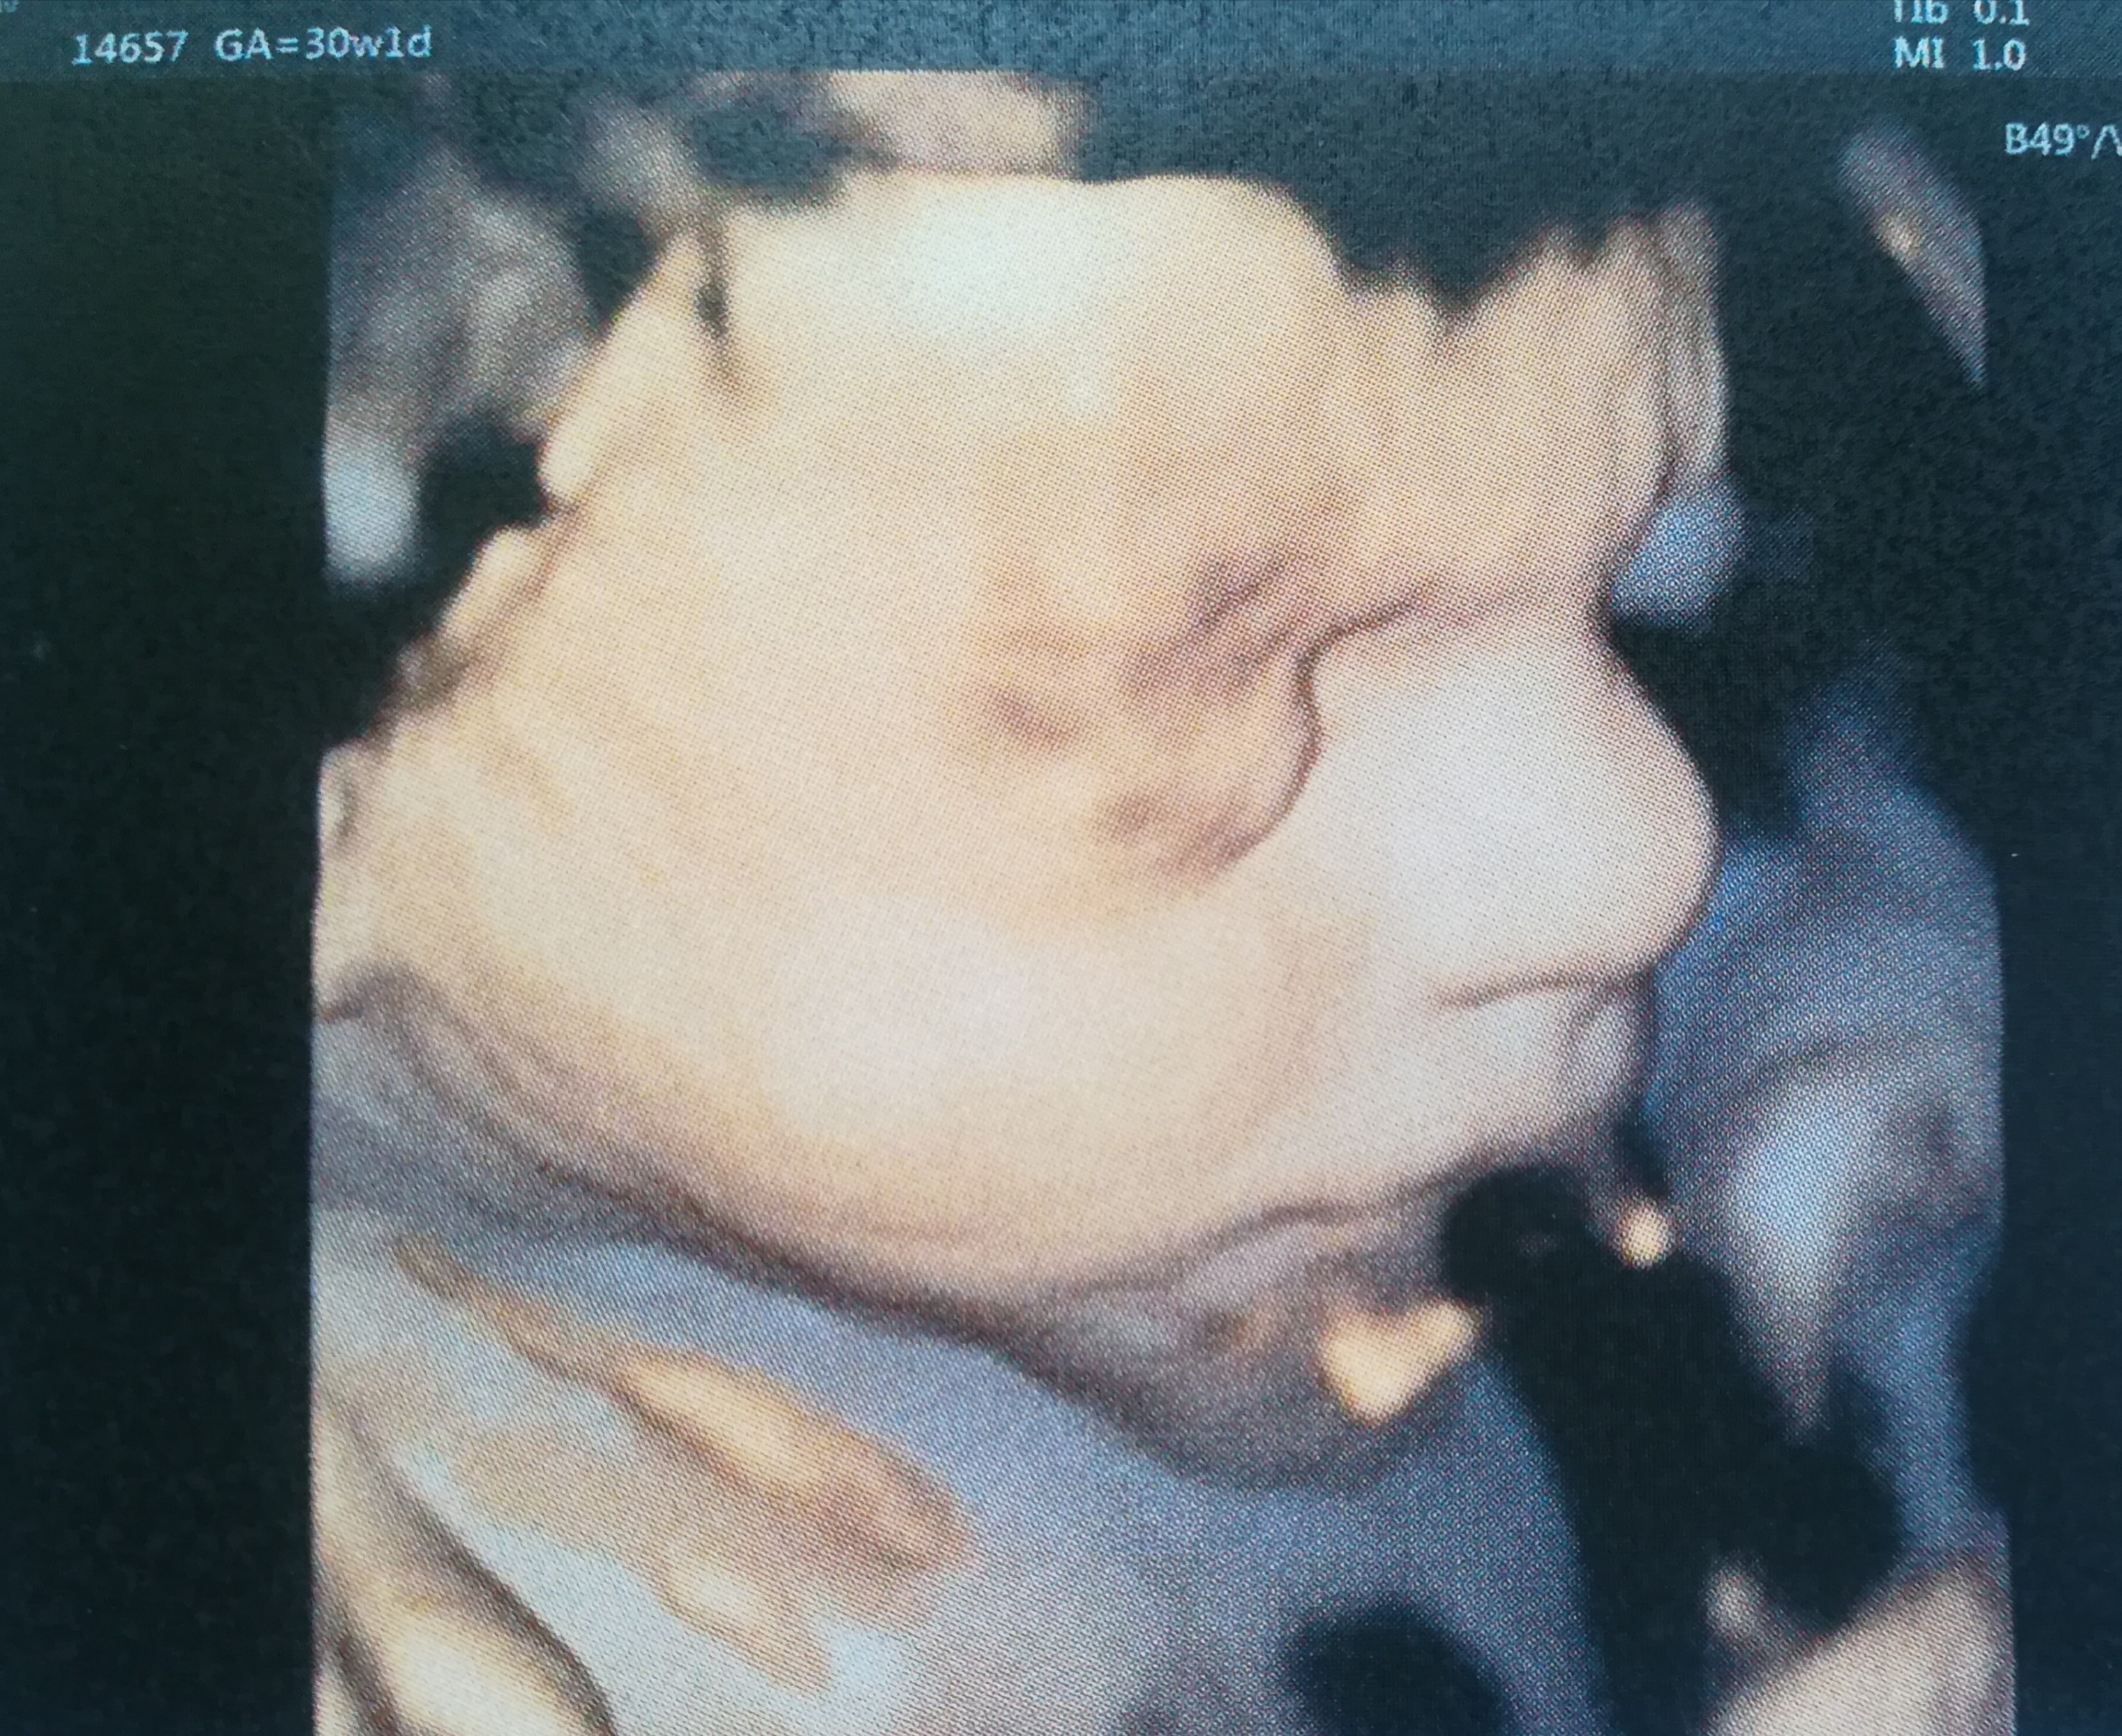

Tamizka ale masz cudenko w brzuchu [emoji7][emoji7][emoji7]Ojj dzieje się dzieje

Jutro zaczynamy 32tc

Stasiu rośnie - waży już prawie 1.5 kg a my nie możemy się doczekać kiedy już będzie z nami [emoji173]️[emoji173]️[emoji173]️

Ściskam Was wszystkie baaaardzo mocnoZobacz załącznik 907515 Zobacz załącznik 907516 Zobacz załącznik 907517